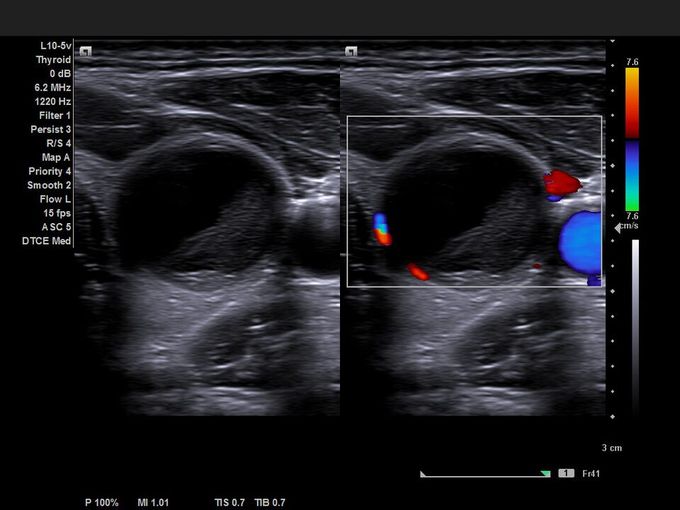

Кроме новой техники, можно заказать восстановленные медицинские системы: ультразвуковые сканеры, томографы, флюороскопы, ангиографы и хирургические установки С-дуга.